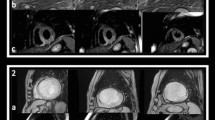

Cardiovascular magnetic resonance protocol

All patients underwent CMR at 1.5 Tesla (Siemens Healthineers, Aera-Magneton, Erlangen-Germany). All studies were performed using dedicated cardiac software, 32-channel phased-array surface receiver coil and ECG triggering. Cine images were acquired using a breath-hold balanced steady-state free-precession (bSSFP) in long-axis and short-axis views. A stack of short-axis slices was acquired to quantify left ventricular (LV) volumes, mass and ejection-fraction. T2-mapping data were acquired by breath-hold T2-prepared bSSFP in the same orientation of short-axis cine images [14]. T2-maps were readily evaluated by an experienced operator during CMR scan, and a single short-axis target-slice was selected in the middle of infarction (Supplemental-Material). Native and post-contrast T1-mapping data were acquired in the target-slice using ECG-triggered breath-hold MOdified Look-Locker Inversion Recovery (MOLLI) sequence with a 5(3)3 and 4(1)3(1)2 sampling scheme for native and post-contrast T1-maps, respectively [16]. Ten minutes after 0.2 mmol/Kg i.v. bolus of Gadobutrol (Gadovist, Bayer Healthcare, Berlin, Germany), late gadolinium enhancement (LGE) images were acquired using a 2D breath-hold phase-sensitive segmented inversion-recovery gradient echo in the same orientations of cine images. Inversion-time was individually optimized to null normal myocardium. In the target-slice, post-contrast T1-mapping was acquired at the end of LGE imaging (> 15 min after Gadobutrol bolus injection). Sequences and protocol are detailed in the Supplemental-Material.

Differences of AAR, infarct size and microvascular damage and LV functional parameters according to the time between revascularization and CMR

Results are summarized in the Table 2. AAR remained stable across TRevasc-CMR tertiles (Fig. 2). Overall 46 (28%) patients showed IMH on T2-mapping. Occurrence and extent of IMH did not differ among TRevasc-CMR tertiles. IS and occurrence and extent of MVO as well as myocardial salvage index were comparable throughout TRevasc-CMR tertiles (Fig. 2). LV end-diastolic volume index increased slightly across TRevasc-CMR tertiles, so that patients in Tertile-3 patients had larger volume than those in Tertile-1. LV end-systolic volume index, regional and global systolic function parameters were comparable across TRevasc-CMR tertiles.

T2 relaxation times in infarct and remote regions

Recent reports generated intense discussion on the dynamic changes of CMR-derived measures of ischemic damage in early post-STEMI phase with particular emphasis on myocardial edema. In elegant experimental studies [6, 7, 9], Fernàndez-Jiménez et al. showed that edema features a bimodal pattern after reperfusion. An initial wave of edema appears abruptly and very early (≤3 h) to be attenuated at 24 h and followed by a second edema wave peaking at 4 to 7 days. The same group described this bimodal pattern in a selected cohort of 16 reperfused STEMI patients undergoing serial CMR (8). In patients, the authors found that T2 values within the ischemic region, as measured by T2-mapping, varied consistently throughout the post-reperfusion phase paralleling the experimental results. Accordingly, AAR, as quantified by T2-weighted short-TI (T2w-STIR), changed substantially with the timing of CMR being significantly lower at 24 h than at hyper-acute (≤3 h) or at 4 and 7 days after reperfusion. In line with these findings, we observed that T2 of the infarct increased with the increase of timing of CMR after revascularization, with a steep augmentation between Tertile-1 (median: 1.0 day) and Tertile-2 (median: 2.7 days) without further change between Tertile-2 and Tertile-3 (median: 5.3 days). However differently from the above study, we found that T2-map-derived AAR did not vary with the timing of CMR after PPCI. This discrepancy can be ascribed to the differences in study populations and, most importantly, to the different techniques utilized for AAR quantification. While Fernàndez-Jiménez’s et al. utilized T2w-STIR, we used T2-mapping, which allows more robust, precise and reproducible estimation of infarct-related edema as compared to T2w-STIR [14, 15]. Different from T2w-STIR imaging, T2-mapping consents to measure T2 lengthening of the ischemic tissue due to increased water content, rendering this techniques particular sensitive to subtle changes in T2 relaxation times [14, 17, 19]. Differently, T2-weightening relies on relative signal intensity differences between ischemic and remote myocardium, which are influenced by several factors in addition to edema per se, such as specific T2-weightening parameters, motion-related signal loss in the lateral wall or selection of window/leveling to display images [15]. Accordingly, slight differences in T2 relaxation times between ischemic and remote myocardium, such as those reported in the experimental and clinical studies by Fernàndez-Jiménez et al. [6,7,8,9] at 24-h after reperfusion, might have been overlooked by T2w-STIR leading to underestimation of AAR. In our study, T2 values of infarct myocardium exceeded largely those of remote region irrespective of the time interval between revascularization and CMR, the presence or absence of IMH, and pre-PPCI residual blood flow in the myocardium at risk. Accordingly, we were able to quantify AAR on T2-maps using a semi-automatic threshold-based algorithm in the overall population and specific subgroups [17]. Moreover, the pattern of T1 values in infarct and remote myocardium paralleled closely that of T2, corroborating our study results. Experimentally T1 relaxation time increases in parallel with increasing myocardial water content, and prolonged T1 has been reported in myocardium at risk in STEMI patients [20, 21].